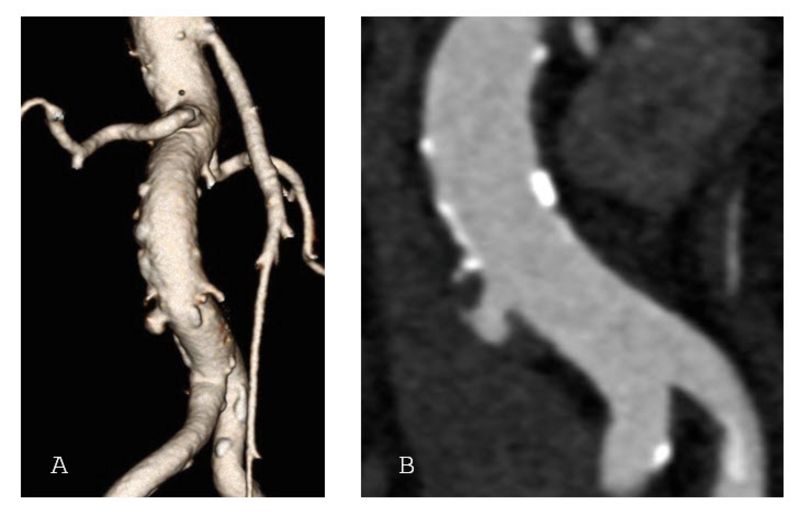

Ein penetrierendes Aortenulkus ist ein Defekt der inneren Gefässwand der Hauptschlagader, verursacht durch Arteriosklerose. Dabei dringt die Gefässverkalkung durch die innere Schicht der Aorta ein und kann zu Aussackungen oder sogar zu einem Riss (Ruptur) führen.Im Gegensatz zu einem Aortenaneurysma, das eine Aufweitung der gesamten Arterie beschreibt, handelt es sich bei einem Aortenulkus um einen lokalisierten Defekt der Gefässwand. Besonders im Bereich unterhalb der Nierenarterien ist diese Erkrankung bisher wenig erforscht.

In der Studie wurden 260 Patientinnen und Patienten zwischen 2018 und 2022 behandelt. Das Durchschnittsalter betrug 74 Jahre, die Mehrheit war männlich. Bei rund drei Vierteln der Patientinnen und Patienten wurde das Aortenulkus zufällig entdeckt, bei einem Viertel hingegen aufgrund akuter Beschwerden wie Bauchschmerzen oder gar einer Ruptur diagnostiziert. Fast alle Patientinnen und Patienten erhielten eine endovaskuläre Therapie, also eine Behandlung über Katheter und Stentprothesen ohne Bauchschnitt. Nur einzelne mussten offen operiert werden.